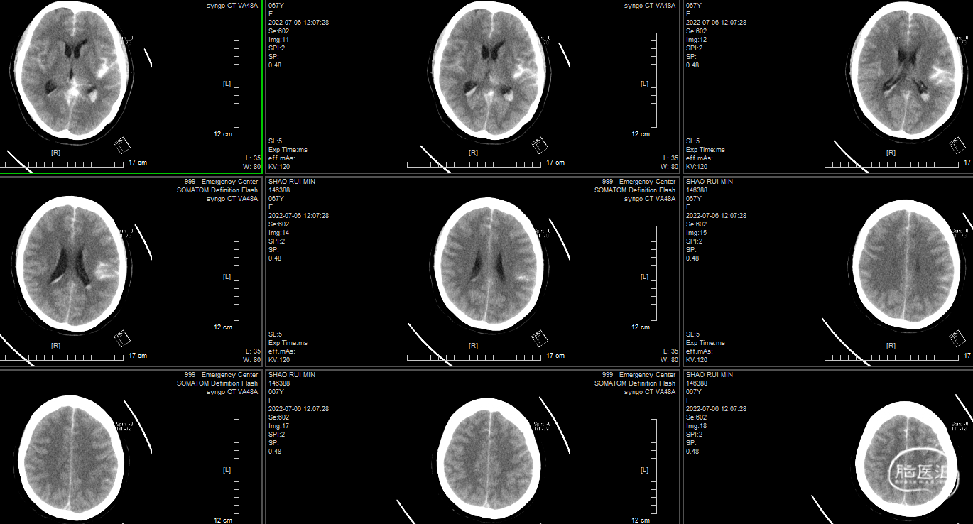

术后第三天查核磁:动脉瘤术后改变,蛛网膜下腔、脑室积血。双侧颞顶叶散多发脑梗塞。考虑左侧肢体活动不利为右侧脑梗塞所致。

术后第三天头颅MRA示:血管通畅。

2022-7-8术后第三天,语言正常,MRI右侧脑梗塞,考虑血管痉挛所致。腰穿!